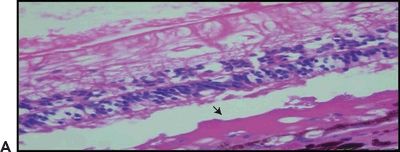

Choroidal also known as subretinal neovascularization (CNV) is one of the main features of wet AMD. The new vessel formation extends from the choroid into the thickened portion of the BM or from the margins of the optic nerve head (40). Studies have confirmed that a prior break in the BM is not necessary for vessel proliferation because the new vessels can make their way through it by themselves (41). CNV is often seen in retinas in which softening and confluence of drusen have taken place (42). In histologic sections, Albert et al. (11) described the following findings: (a) breaks in BM; (b) a granulomatous inflammatory pattern with macrophages, lymphocytes, and fibroblasts; (c) basal laminar deposits and soft drusen; and (d) RPE depigmentation, hypertrophy, hyperplasia, and folding. On electron microscopy, both mature and newly formed capillaries have fenestrations similar to their choriocapillaris precursors. They also have high permeability to fluorescein and may cause leakage or fluorescein blockage (43). Even though they are initially very small, are nondetectable, and have capillary characteristics, they acquire arterial and venous features with time. Ophthalmoscopically, they can either be seen through the atrophic RPE or hidden underneath fibrous grayish tissue or RPE hypertrophy. CNV can be localized to the macula, peripapillary retina, or peripheral retina. CNV can be restricted to the BM (Fig. 5.4A and B) or trespass the RPE and grow into the subsensory space associated with fibroblastic RPE metaplasia and migration of macrophages (33). Anastomosis between choroidal and retinal vessels can develop. This characteristic is often seen in late stages of AMD when the disciform scar is well established (2). The neovascular membranes can be recognized in the fluorescein angiogram as a fine network of vessels with early filling, associated with exudation and subretinal hemorrhage. These specific elements are toxic for the RPE and photoreceptors, and they may lead to RPE detachment, proliferation of fibrous tissue, cystoid macular edema, and occasional circinate retinopathy (33,44,45). In this setting, fibroblasts can be identified invading the hematoma. Also, the surviving RPE cells are transformed into elongated spindly cells while the overlying photoreceptor atrophy resulting in a submacular nodule, plaque, or fibroglial scar tissue that contracts and distorts the retina (40).

Figure 5.4 Wet AMD. A. Histologic section shows CNV at the BM. Retinal pigment epithelium (RPE), choroid (C), and sclera (S). H&E stain 40×. B. Magnified view of the choroidal neovessels (asterisk). H&E stain 60× (Courtesy Zárate JO, Alvarado M© 2011. Unpublished data.)